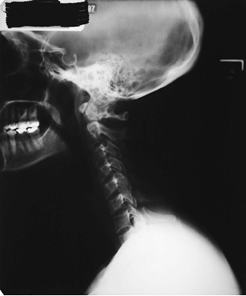

正常なコブ角を持つ人の頸椎レントゲン 線維筋痛症患者さんの頸椎レントゲン

線維筋痛症の平均頸椎弯曲は6.4 ± 5.2度、対照群は13.8 ± 7.4度で7度以上の差をもって有意差(p < 0.001:統計学的に両者に差がある)があったとのことです。 21°未満の弯曲が正常範囲から外れていると考えると、線維筋痛症の患者さんのみならず、他のリウマチ疾患をもっている患者さんも頸椎の前弯の角度が少ない結果となっています。

しかし、この中で、頸椎がほぼ直線である(論文では10度以下の弯曲)人は、線維筋痛症患者さん129名(83.2%)に対し、対照群患者さんは37名(32.2%)と、こちらも統計的な有意差をもってストレートネックの割合が線維筋痛症の患者さんで高い割合であったとのことでした(p < 0.001)。